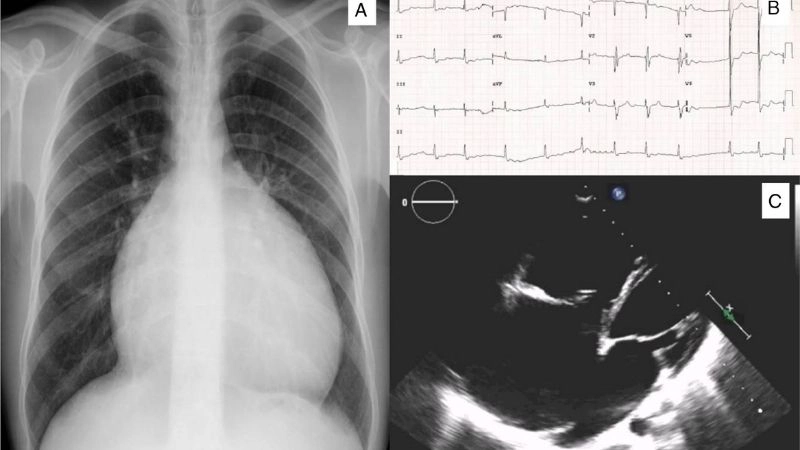

Images visual examples of Uhl's anomaly

Uhl’s anomaly is a rare congenital heart condition characterized by the near-complete absence of the right ventricular myocardium, resulting in a thin-walled and weakened heart chamber.